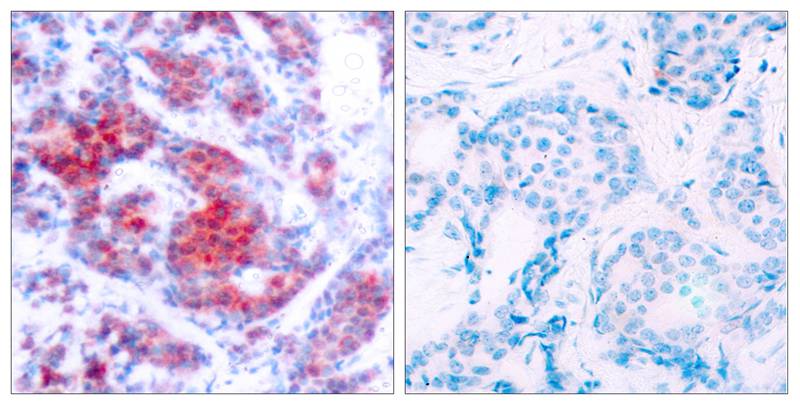

分类: 科研抗体货号: P40098别名: Tumor suppressor p53; Phosphoprotein p53; Antigen NY-CO-13; TP53;应用: WB,IHC,IF反应种属: Human